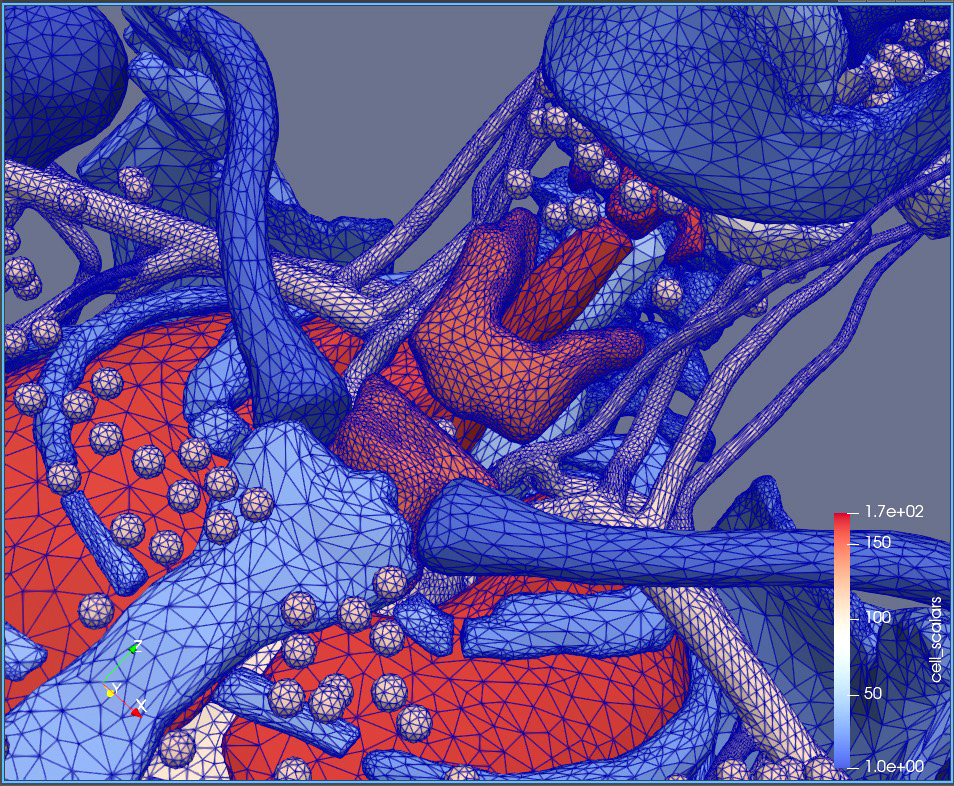

One of the students in their research group is Megan Chesal, who is a LaSpace graduate fellow working toward a master’s degree in medical physics with plans for a Ph.D. where her continued research as part of the SpaRTAN group will dive into artificial intelligence and machine learning. Originally from Natchitoches, Louisiana, she is helping the group develop intricate, quite beautiful, and fully digital 3D visualizations of human bodies, called computational phantoms. They can be used to study and predict the biological effects of various types of radiation (different particles and energies) on specific organs, for example. By creating a computerized anatomical man (CAM) and a computerized anatomical female (CAF), Chesal is helping her team see differences in outcomes between men and women. While she got her bachelor’s degree in physics at LSU, her work is now merging with art and biology.

Master’s student Megan Chesal is helping Chancellor’s group develop intricate, quite beautiful, and fully digital 3D visualizations of human bodies, called computational phantoms. They can be used to study and predict the biological effects of various types of radiation (different particles and energies) on specific organs, for example.